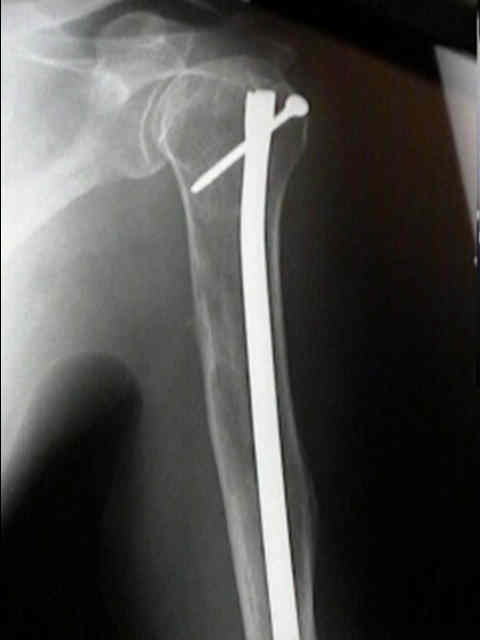

Humerus 10

Humerus 11

Humerus 12

Surgical Fixation

mmyl1 mmyl2